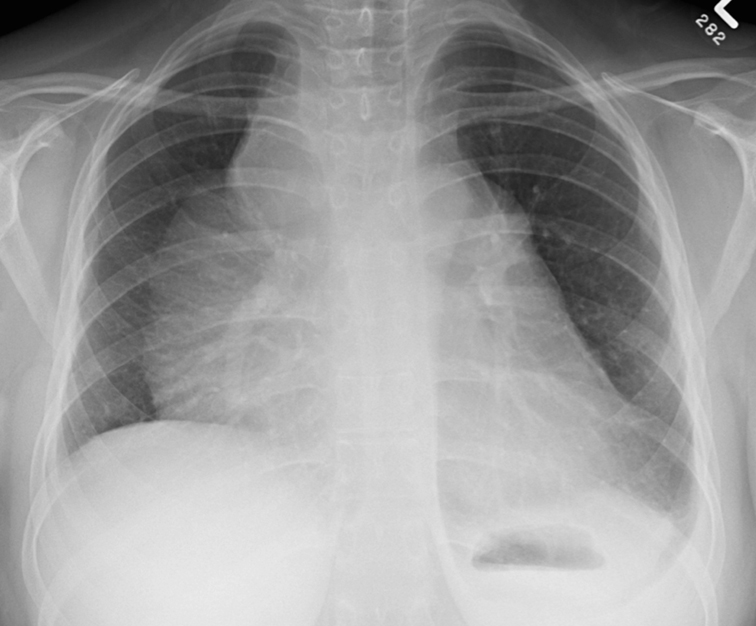

Hilum overlay sign